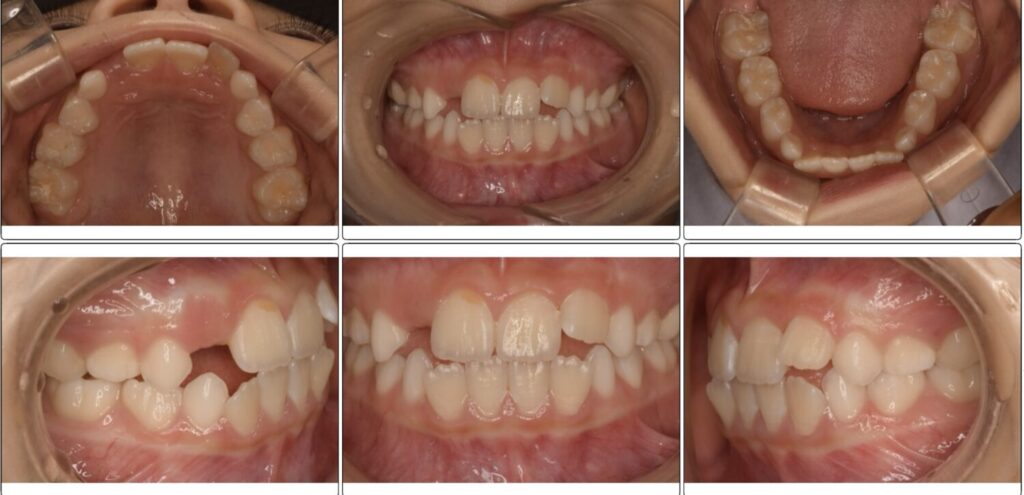

一番最初当院に来院されたきっかけは下の4本の歯が平坦に並んでいることと、上の2番目の生えてきている歯が唇の方から生えてきて入る場所がないことがきっかけでした。

3ヶ月後の変化の写真です。

平坦だったのはなくなり綺麗なアーチになりました。

マウスピースをつけることで飲み込み方の改善や力のかかり方が変わるため変化が起きやすいです。

アクティビティーやマウスピースを行なってくれていると変わります。

上の歯並びも3ヶ月後に見ると左の前から2番目の歯が綺麗に入っています。

ですが反対側の歯がまだ入りません。

でも確実に顎は大きくなってきています!